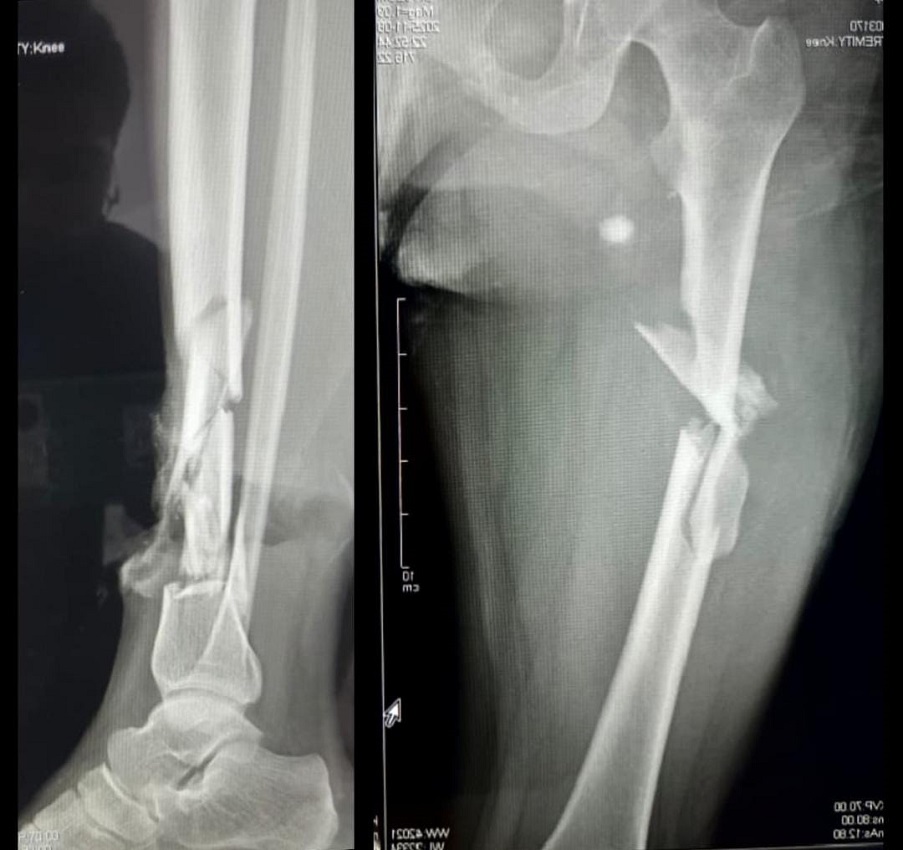

Su hija Jenny fue llevada al hospital Germán Busch y luego derivada a la Unidad de Terapia Intensiva por el grave cuadro clínico; sufrió una hemorragia interna, perforación intestinal, cuatro fracturas graves en el pie y una en la mano. Julia dijo que “todo está roto”.

Jenny batalla por salvar su vida. El pronóstico no es nada alentador a causa de sus fracturas. La cirugía aun no es posible, ya que los médicos le dijeron a Julia que su hija debe curarse de las complicaciones secundarias, como las infecciones en los pulmones, la anemia severa y los problemas en la sangre. “No hay cuando se sane mi hija y la estamos viendo, queremos curarla, pero me parece que se está pudriendo”, sollozó.